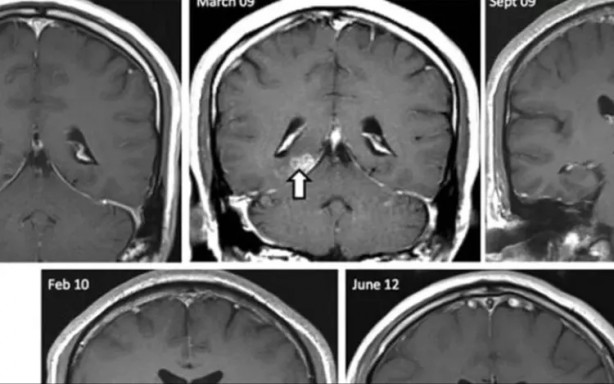

Sürekli olarak devam eden baş ağrısı şikayetiyle doktora başvuran bir adamın alnından çıkanlar doktorları da şaşkına döndü.

Rusya’nın Novorossiysk kentindeki bir hastanede akıllara durgunluk veren bir olay yaşandı. İsmi açıklanmayan hasta bir türlü geçmeyen baş ağrısı şikayetiyle doktora başvurdu.

Doktorlar yaptıkları incelemelerde hastanın alın bölgesinden şakaklarına doğru uzanan yabancı bir cismin varlığını gördü.

15 CM UZUNLUĞUNDA SOLUCAN Cerrahi operasyonla doktorlar hastanın şakaklarının etrafındaki derinin altına sıkışan 15 cm uzunluğunda bir solucanı çıkarttı.

“SİVRİSİNEK ISIRIĞINDAN ŞÜPHELENİYORUZ” Rusya’daki hastaneden yapılan resmi açıklamada, “Kaş bölgesindeki ağrılı şişlik şikayetiyle hastanemize başvuran bir hastanın cerahatli bir iltihaplanma sürecinden şüpheleniyorduk. Cerrahi müdahalenin ardından 15 cm uzunluğunda ince ve beyaz bir solucan bulundu. Sivrisinek ısırığından şüpheleniyoruz. Çünkü dirofilariasisin taşıyıcıları genellikle sivrisineklerdir” dedi..